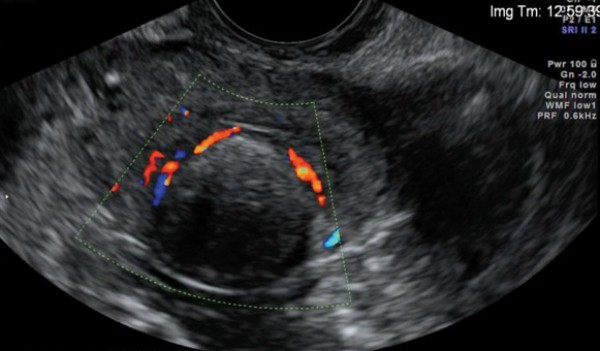

Upon hearing the diagnosis „uterine fibroid“ women tend to panic and immediately associate it with a tumor and surgical intervention. In some cases it can indeed be a rather unpleasant condition, but it is certainly not cancer. This benign neoplasm arises from the spontaneous growth of uterine muscle tissue as a result of hormonal imbalance, stress, inflammation, miscarriage, etc. There can be a number of causes. In most cases they are not dangerous, but it depends on their size and location.

Traditional medicine can actually help even in severe forms of this female condition. It is a remedy based on aloe and honey, which the woman took in a certain amount three times a day for one month. It was a great surprise to the doctors when no fibroid was found on the ultrasound at the next check-up! What will you need to prepare this mixture?